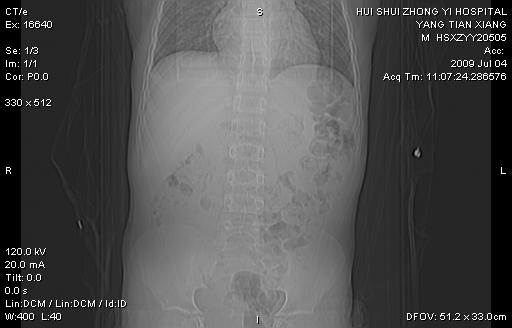

肝右叶胆管内见条状高密度影,脾脏增大,双肾上腺无异常;右肾正常结构消失,其实质内见类圆形低密度灶,ct值范围0-6hu,界清,右输尿管全程伴行多发低密度灶,界清,膀胱壁增厚,腹盆腔未见确切肿大淋巴结。

考虑:1、肝内多发胆管结石并肝内胆管扩张。2、右肾、输尿管多发脂肪瘤,多发平滑肌瘤?建议ct增强检查。4、膀胱壁增厚。

1)考虑右侧巨输尿管畸形。2)肝内胆管多发性结石。3)脾大。

右侧巨输尿管并神谕积水,左肾代偿性肥大,脾大,肝内胆管多发结石并胆管扩张。